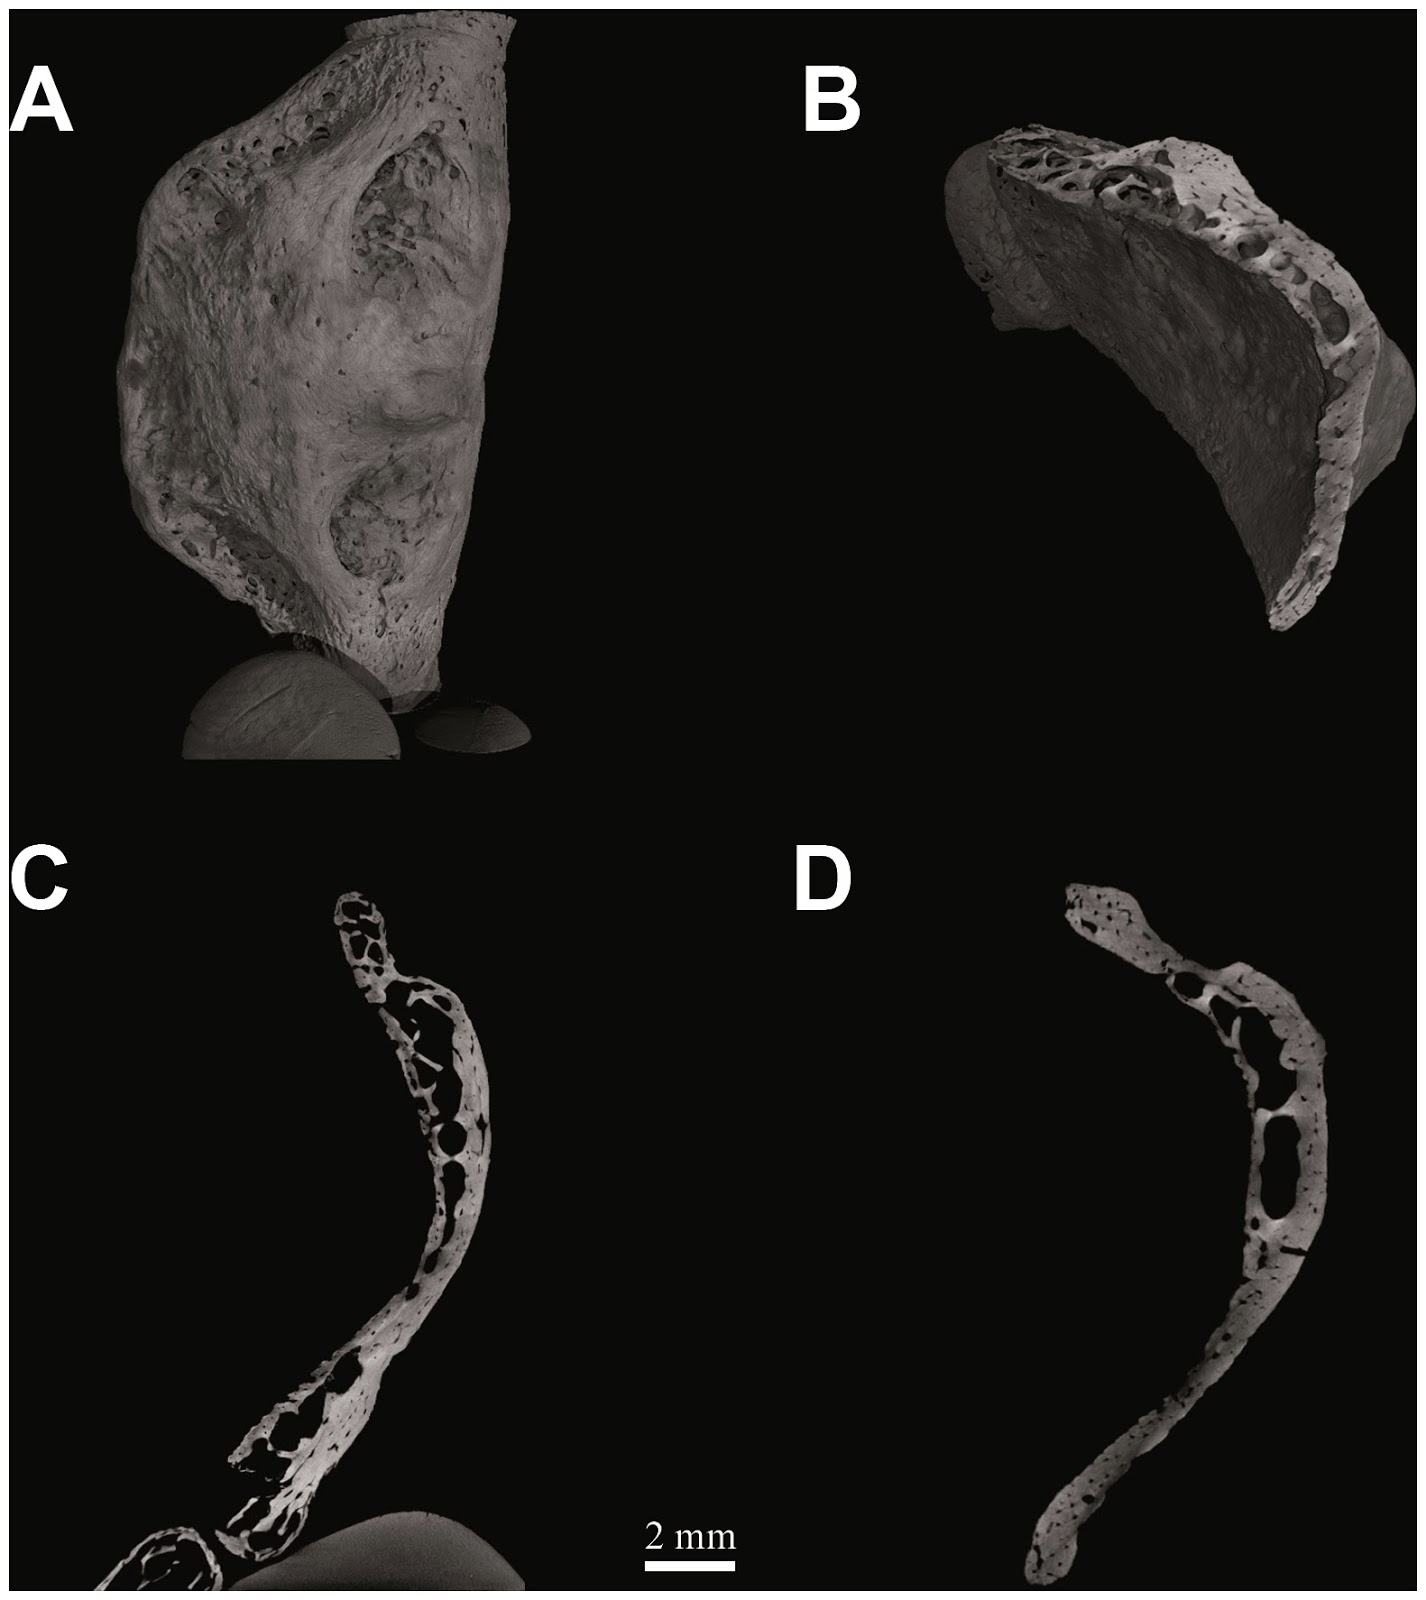

Kebara 2. Tomografia computarizada

Ruggero D’Anastasio, Stephen Wroe, Claudio Tuniz, Lucia Mancini, Deneb T. Cesana, Diego Dreossi, Mayoorendra Ravichandiran, Marie Attard, William C. H. Parr, Anne Agur y Luigi Capasso han estudiado el hueso hioides neandertal, hallado en 1989, Kebara 2: histología, musculatura y análisis biomecánico computacional con micro-geometría interna, utilizando microtomografía computarizada y simulación de materiales con análisis finitos de elementos.

Este hueso presenta una arquitectura interna y un comportamiento micro-biomecánico muy similar al hioides del HAM. La estructura interna, que se remodela en respuesta a la tensión mecánica a la que es sometido el hueso, revela su función.

La estructura histológica es típica de un hueso sometido a actividad metabólica intensa y constante.

Este resultado es consistente con la capacidad de hablar de los neandertales.